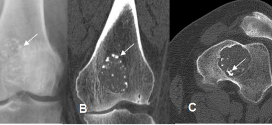

El encondromatosis múltiple. Condrodistrofia (alteración de la Osteogénesis que se traducen por la presencia anómala, irregular, hiperplásica o hipoplásica de cartílago). Asimétrica; afección caracterizada por la proliferación hamartomatosa de cartílago en la metáfisis de varios huesos. La encondromatosis múltiple (o según la terminología de la OMS, el síndrome de Ollier) se define por la presencia de múltiples encondromas con una …